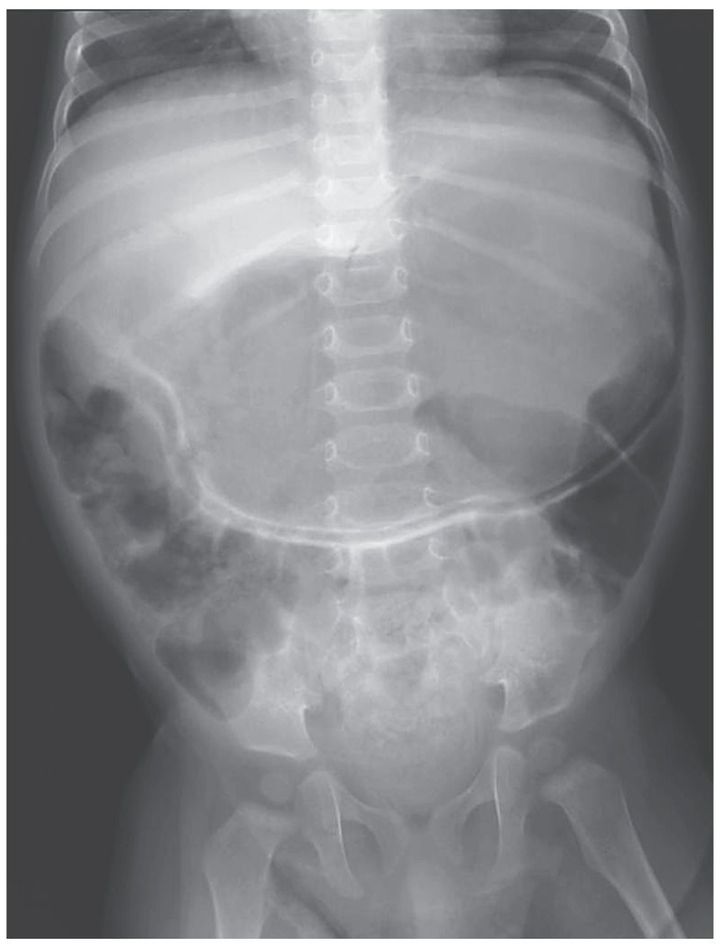

A 10-month-old male infant weighing 7.34 kg (2nd percentile for age and sex) presented with a 4-day history of nonbilious, nonbloody emesis. He had a history of frequent nonbilious emesis and poor weight gain since birth. He had difficulty consuming solid foods and was given a diagnosis of reflux. There was no surgical history. The patient's vital signs were normal, his white-cell count was 12,000 per cubic millimeter, and his abdomen was minimally distended, without tenderness. An abdominal radiograph showed marked gastric emphysema and some gas in the small bowel and colon. Abdominal ultrasonography and computed tomography, performed without the administration of contrast material, confirmed gastric emphysema with no obvious cause. The differential diagnosis included infection, ischemia, and gastric-outlet obstruction due to volvulus, annular pancreas, intestinal malrotation, and duodenal hematoma or stenosis. Laparotomy revealed diffuse gastric and omental emphysema resulting from duodenal stenosis. A duodenoduodenostomy was performed. Within 4 days after surgery, the patient was able to ingest formula and was discharged on day 6. A month later, he was eating age-appropriate foods without emesis.